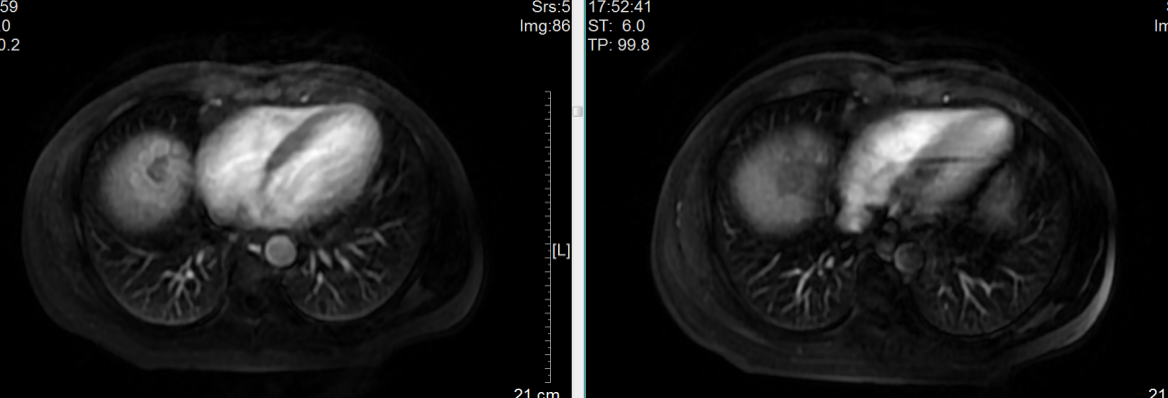

磁共振检查显示肿瘤位处肝脏膈顶部